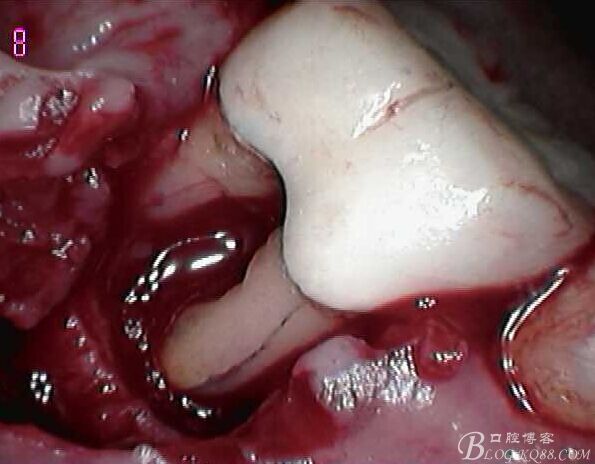

頰側翻瓣見,頰側骨壁完全缺損,同時見近遠中根都有縱向裂紋,

無法保留,

建議拔除C6,延期種植,

拔出后可見頰舌側都有縱向裂紋

翻瓣,拔除C5,跟尖端有吸收